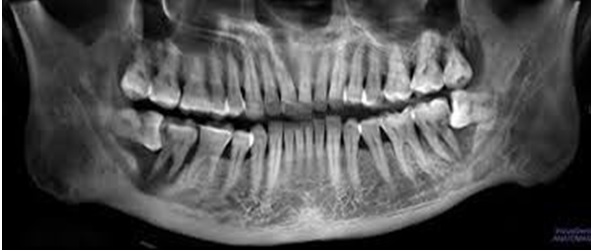

Trong thực hành lâm sàng Răng Hàm Mặt, răng khôn mọc lệch thường gặp ở các dạng sau:

- Mọc lệch gần (Mesioangular impaction): Răng nghiêng về phía răng số 7.

- Mọc lệch xa (Distoangular impaction): Răng nghiêng về phía sau cung hàm.

- Mọc ngang (Horizontal impaction): Răng nằm ngang trong xương hàm, có thể chèn vào răng số 7.

- Mọc thẳng nhưng bị kẹt (Vertical impaction): Răng mọc gần đúng trục nhưng không thể trồi lên hoàn toàn do bị cản trở bởi xương hoặc mô lợi.

Dù ở dạng nào, răng khôn mọc lệch cũng có thể gây đau và nhiều biến chứng nếu không được theo dõi, xử trí kịp thời.

Hình ảnh các loại răng khôn mọc lệch